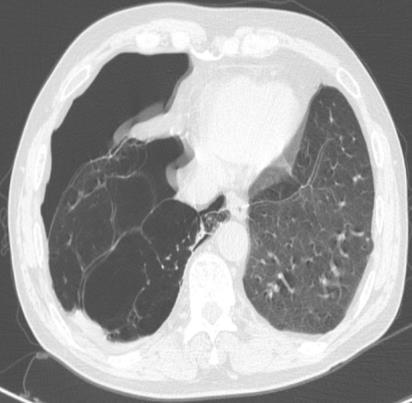

• 右肺中叶病变的临床特征分析(附709例报告)

2026, 32(3):45-50. DOI: 10.12235/E20250294

摘要 (42) HTML (59) PDF 1.50 M (41) 评论 (0) 收藏

摘要:目的 探讨右肺中叶支气管异常患者的人口学特征、临床表现、病因、影像学表现和支气管镜下表现。方法 回顾性分析2015年5月-2025年4月于该院在支气管镜检查中表现为右肺中叶异常改变的709例患者的临床资料,统计分析病因和临床特征。结果 709例患者中,男465例,女244例。男患者年龄(63.1±9.1)岁,明显高于女患者的年龄(60.9±11.5)岁,差异有统计学意义(P < 0.05)。临床表现主要包括:咳嗽、气促、咯血、痰中带血和胸痛,9.9%的患者未出现临床症状。根据年龄范围进行分组,将年龄 > 55岁的542例(76.4%)患者纳入高龄组,≤55岁的167例(23.6%)患者纳入低龄组,高龄患者明显多于低龄患者,差异有统计学意义(P < 0.05)。高龄组中,常见的3种病因分别为:肿瘤、炎症和结核。支气管镜下表现为:右中叶新生物、黏膜肥厚或肿胀、管腔狭窄和瘢痕闭塞等。结论 右肺中叶病变的患者采用影像学和支气管镜相结合的方式,对明确病因和指导临床治疗有重要意义。